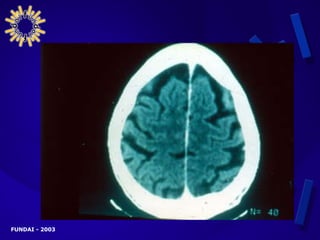

MANIFESTACIONES CLÍNICAS AVANZADAS   PRESENTACIÓN NEUROLÓGICA CENTRAL Cefaleas Fiebre Trastornos de conciencia Convulsiones Rigidez de nuca Signos meníngeos Signos focales